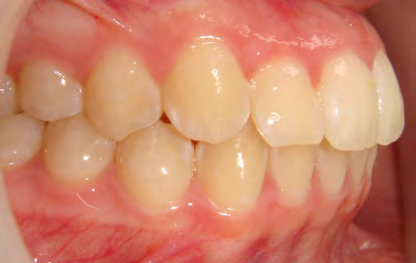

All of the patients below had been told they required extractions by orthodontists, some insisting that they could not be treated without extractions.

They were all treated without extractions, head gear or facemasks at Vakresmil and represent just a small sample of cases treated between 2004–2014.

The patient below had severe crowding of both upper canines and the lower right 5. The upper 4’s and 2’s were actually in contact.